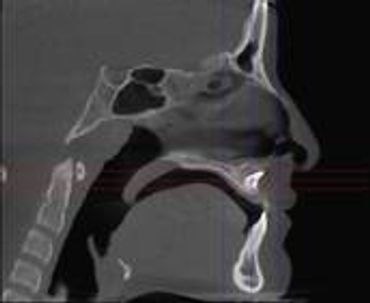

What is CBCT- Cone Beam Computer Tomography?

CBCT is a digital x-ray scanner specifically designed for scanning the head and jaws. The scanner rotates 360 degrees around the patient's head in a matter of seconds. The x-ray is a low energy fixed anode tube similarly used in panoramic machines. This method reduces radiation scatter common to most conventional x-rays. The cone shaped x-ray provides 360 views that can be presented in 2D image and 3D volume for advanced planning and diagnostic support.

[Why the need for a CBCT?]

This one scan provides more images than plain film conventional imaging, with complete visualization of the patient's entire maxillofacial region. These images clearly display TM disorders, impacted teeth, critical bone and tooth relationships, oral- nasal airways, para-nasal sinus, mandibular canal and difficult to see pathologies within one volume. The user friendly software system reconstructs true size, distortion free, high resolution images.

FOV Field of View Are options that allows us to choose the best x-ray beam size/ratio for a study.

We can isolate an area from 8cm x 8cm to as large as 23cm x 17cm. We can customize the field as well.

Voxel: We also can choose the voxel size of the scan. Voxel derives from the terms combine from Pixel and Volume. The best depiction that I can give you is a rubics cube.

The smaller the cube the higher definition of the scan. Our average scan we take is at a .25mm voxel. This allows us to make cross-sectional slicings down to .25 mm, and we typically will measure and print at 1mm. (depending on the study ordered).